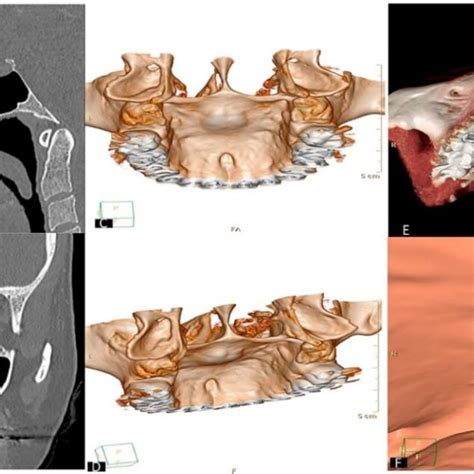

Si notas un bulto duro en el centro del paladar, es muy posible que se trate de un torus palatino. El torus es básicamente un crecimiento excesivo de hueso en el paladar duro. Suele aparecer en la línea media del paladar y tiene una consistencia ósea (firme al tacto). No duele ni crece rápidamente, más bien se desarrolla lentamente a lo largo de los años. Mucha gente convive con un torus palatino sin darse cuenta, ya que suele ser asintomático y benigno. De hecho, se considera una variante anatómica normal en un porcentaje de la población.

Tratamiento: En la mayoría de los casos no hace falta tratar un torus palatino. Solo recomendaríamos su extirpación quirúrgica si crece tanto que interfiere con la masticación, la pronunciación o la colocación de una prótesis dental, o si al paciente le molesta para su higiene.